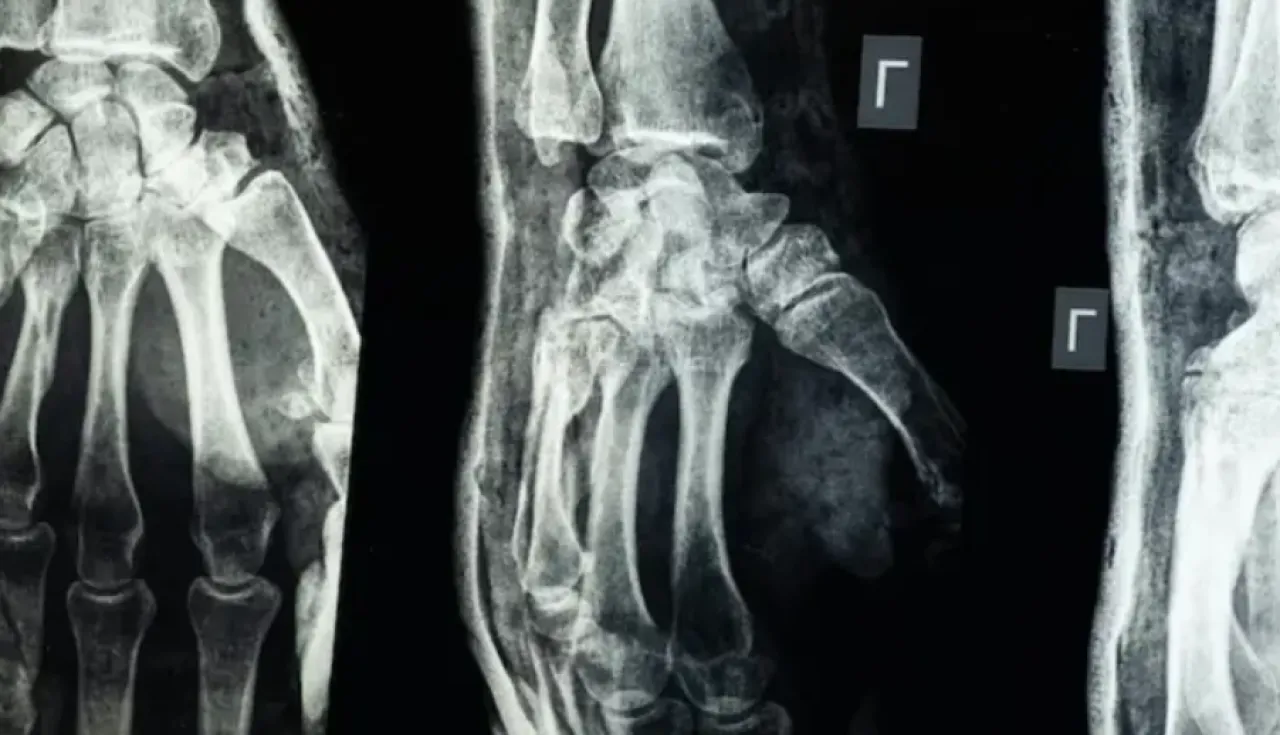

خبرني - أعلن فريق بحثي في مقاطعة تشيجيانغ شرق الصين عن ابتكار طبي جديد يتمثل في "غراء عظمي" قادر على معالجة الكسور وتركيب الشظايا العظمية خلال ثلاث دقائق فقط، في خطوة وُصفت بأنها اختراق علمي في عالم جراحة العظام، بحسب ما نقل موقع "إن دي تي في" NDTV.

وأكدت الاختبارات المعملية أن Bone-02 نجح في تحقيق نتائج جيدة من حيث السلامة والفعالية. وفي إحدى التجارب، أُجريت العملية في أقل من 180 ثانية (ثلاث دقائق)، بينما كانت طرق العلاج التقليدية تتطلب وقتاً طويلاً لزرع صفائح فولاذية ومسامير.

وبحسب الاختبارات المعملية، تمكن الغراء من تحقيق قوة ربط تفوق 400 رطل، وقوة قص تبلغ نحو 0.5 ميغاباسكال، وقوة ضغط تقارب 10 ميغاباسكال. كما أظهرت التجارب على أكثر من 150 مريضاً نتائج ناجحة، ما يعزز احتمالية أن يصبح بديلاً للزراعات المعدنية التقليدية التي تُستخدم في تثبيت العظام. كما يقول العلماء إنه قد يقلل أيضًا من مخاطر العدوى.